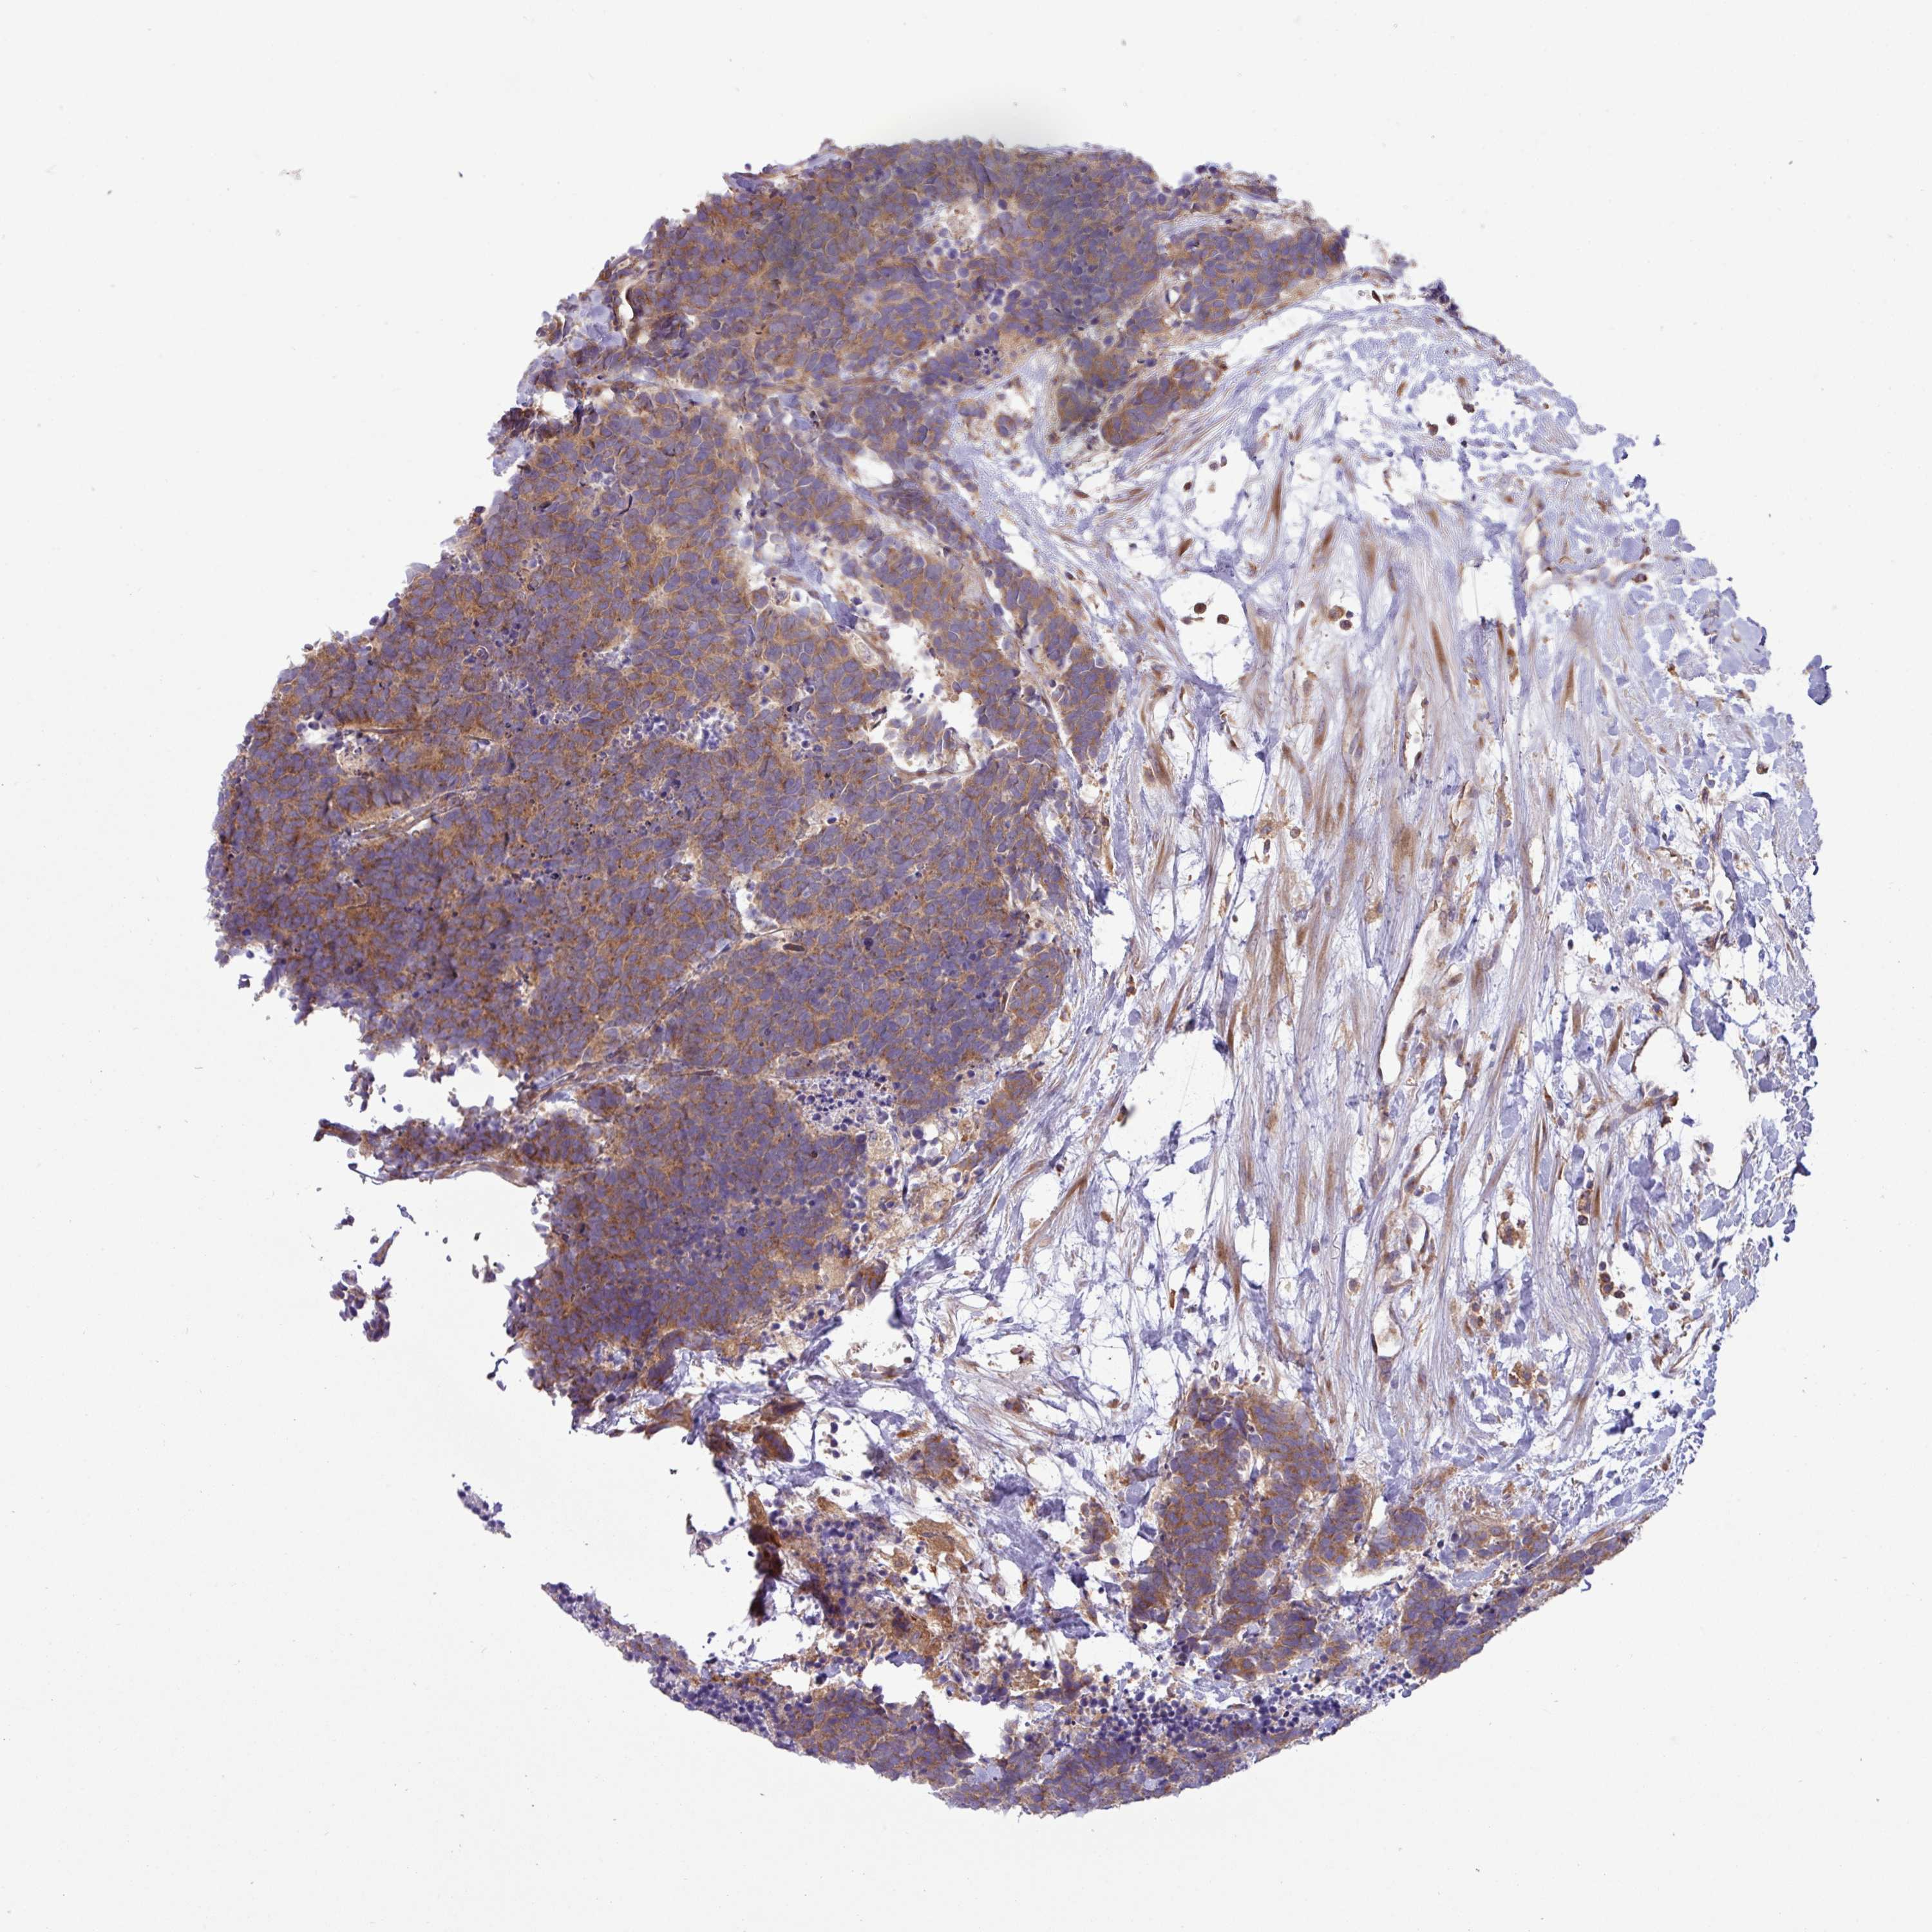

CARCINOID - Protein expressioni

A mouse-over function shows sample information and annotation data. Click on an image to view it in a full screen mode. Samples can be filtered based on level of antibody staining by selecting one or several of the following categories: high, medium, low and not detected. The assay and annotation is described here.

Each image is clickable and will lead to virtual microscopy that enables deeper exploration of all samples and also displays staining intensity scores, fraction scores and subcellular localization as well as patient and tissue information for each sample.

Antibody HPA051077

Staining

Medium

Intensity

Moderate

Quantity

75%-25%

Location

Cytoplasmic/membranous

Carcinoid, malignant, NOS

Carcinoma, NOS